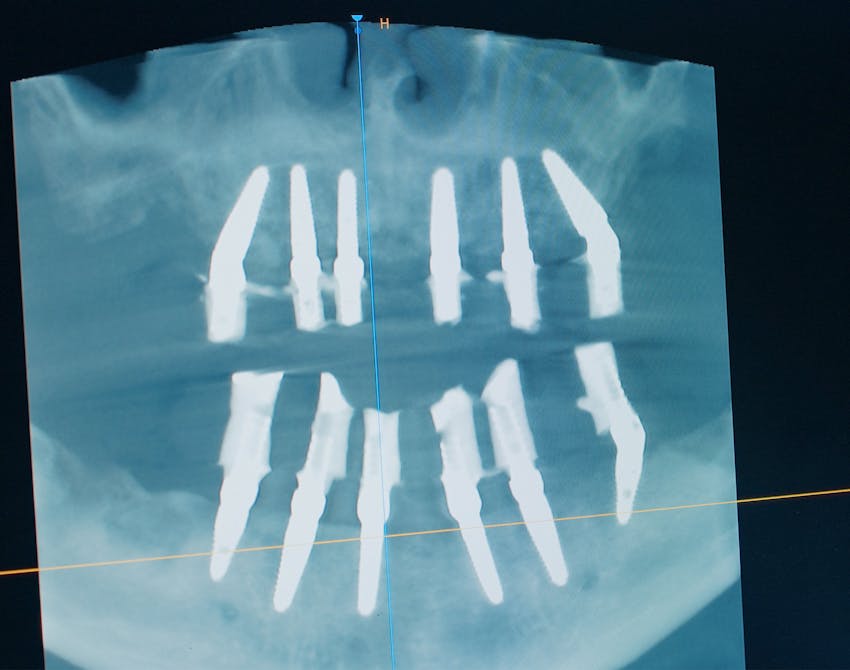

Dental implants are small titanium posts that are surgically placed into the jawbone, serving as artificial tooth roots. Once integrated with the bone through a process called osseointegration, the implant becomes a stable foundation for a custom-crafted crown, bridge, or denture that mimics the look and function of natural teeth. This stability allows for improved chewing ability, enhanced speech, and long-term comfort.

What sets our dental implants in Wellington apart from other tooth replacement options is their ability to preserve jawbone density and facial structure, preventing the bone loss that often accompanies missing teeth. Whether you're replacing a single tooth or a full arch, implants offer unmatched durability, aesthetic appeal, and a more natural feel than traditional alternatives. At our center for cosmetic dentistry, we use advanced imaging and implant techniques to ensure precise placement and lasting outcomes tailored to each patient's needs.